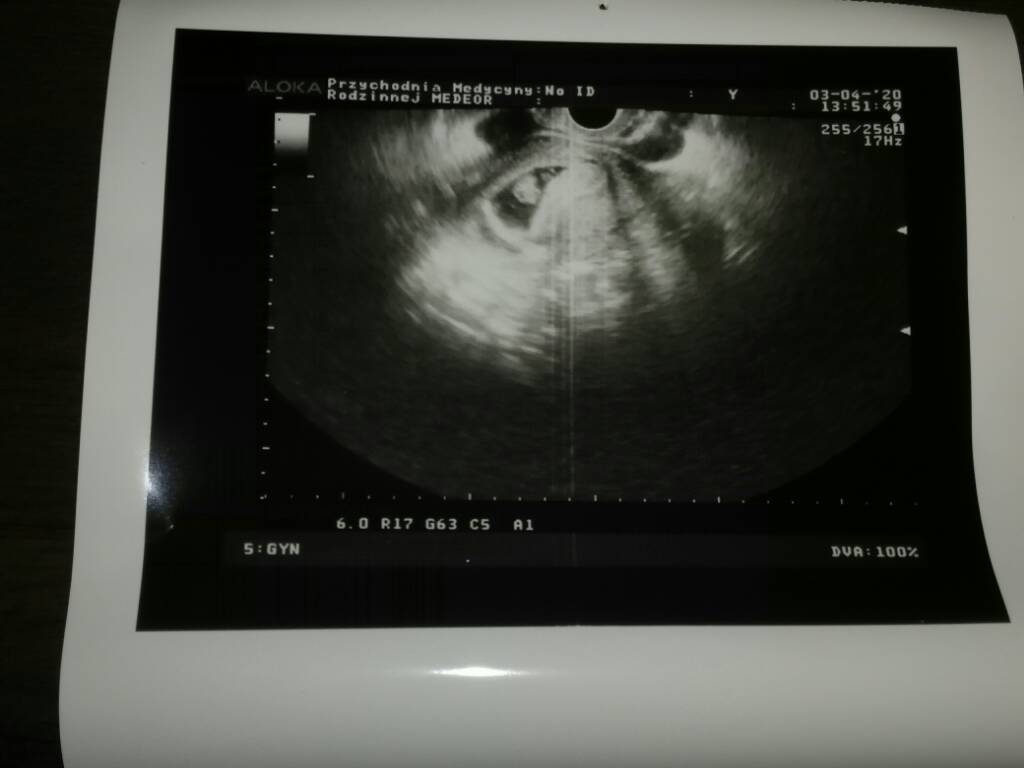

Wracam mega szczęśliwa od pani doktor, jest serduszko, śliczny zarodek mówiła że 7-8 tydzień. Termin 10 listopad. Dziękuję za wsparcie i wiare, że wszystko będzie dobrze. Pani doktor narazie przyjmuje tylko prywatnie więc i tak do niej będe chodzić. Za tydzień kolejna wizyta z wynikami badań i będzie 4 tygodnie zwolnienia z pracy. Wstawiam fotke naszego maleństwa Zobacz załącznik 1101027

Gratulacje, wspaniala wiadomoscWracam mega szczęśliwa od pani doktor, jest serduszko, śliczny zarodek mówiła że 7-8 tydzień. Termin 10 listopad. Dziękuję za wsparcie i wiare, że wszystko będzie dobrze. Pani doktor narazie przyjmuje tylko prywatnie więc i tak do niej będe chodzić. Za tydzień kolejna wizyta z wynikami badań i będzie 4 tygodnie zwolnienia z pracy. Wstawiam fotke naszego maleństwa Zobacz załącznik 1101027